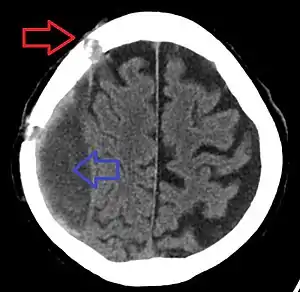

| Chronic subdural bleed with old burr holes | |

Burr hole, also known as trepanation, is a procedure in which a hole is made through the skull.[2] This is done to treat epidural or subdural hematomas when midline shift occurs, the Glasgow coma scale is less than 8, and one pupil has enlarged.[1] While most commonly performed by neurosurgery, It may be done by an emergency physician if the former is not available.[1][3]